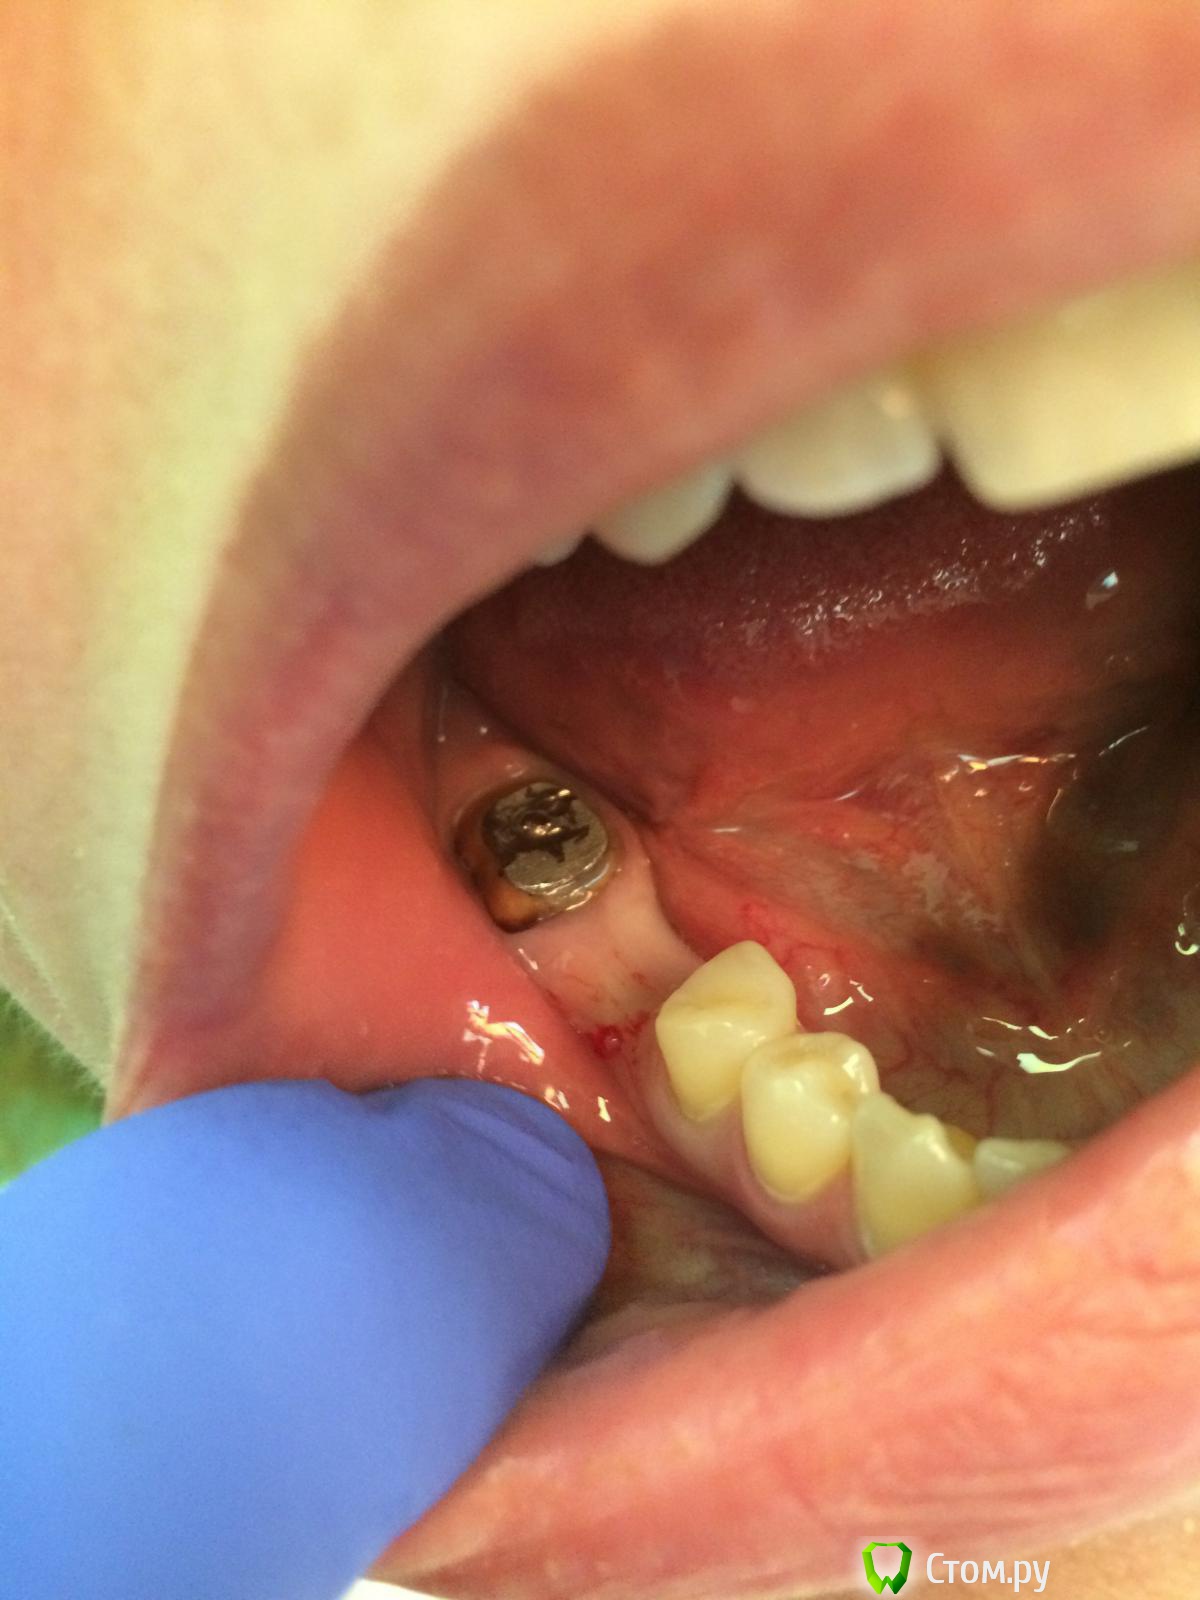

Vadim09 Опубликовано 11 октября, 2014 Автор Поделиться Опубликовано 11 октября, 2014 (изменено) Нашел снимки до удаленияСегодня пришла пациентка, сделал небольшой разрез по гребню, прозондировал, кость есть, но пока не минерализировалась, как говорил stommm.Назначил на середину декабря. Изменено 11 октября, 2014 пользователем Vadim09 Ссылка на комментарий